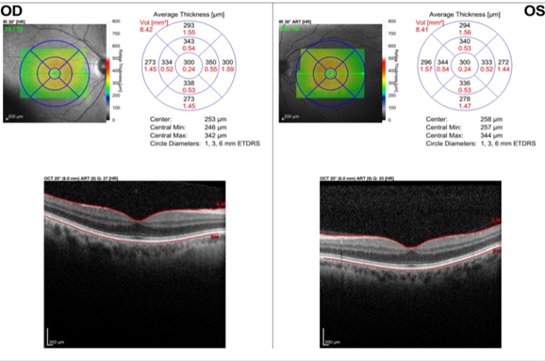

Based on complaints and ocular history, it was hypothesized that his complaint of visual decline in his right eye was likely related to his multiple corneal refractive procedures. The first differential diagnosis that was considered was corneal ectasia. Ectasia should be on the differential list for patients who have previously undergone refractive surgery and have complaints of visual change. There are several risk factors that would lead to an increased likelihood of ectasia. These risk factors include deep ablation, forme fruste keratoconus, steep corneas, or thin corneas (<500 microns).8 As this was a new patient to our clinic, his corneal health was unknown prior to his examination. He did note two separate procedures on his right eye so it was fully possible that there was a significant cumulative ablation. A corneal topography was completed and revealed a topographical pattern consistent with prior laser vision correction. No extreme thinning was noted, nor was any significant irregular astigmatism (Figure 1 & 2). Central corneal thickness was 511 microns and 532 microns in the right and left eye respectively. The topographical pattern was symmetrical across the corneal apex and there were not isolated areas of posterior thinning. The central cornea of each eye was relatively flat compared to the periphery which is consistent with myopic laser vision correction. Macular pathology also was to be ruled out. There were no complaints of distortion or central vision loss, nor was there any noted history of retinal disease or systemic disease typically associated to retinal pathology. Nonetheless, a macular optical coherence tomography scan (OCT) was completed prior to examination and revealed unremarkable anatomy (Figure 3). A normal foveal contour was noted with no sign of retinal pigment epithelium disease, macular edema, or thinning in both eyes.

Figure 3 A macular optical coherence tomography scan (OCT).